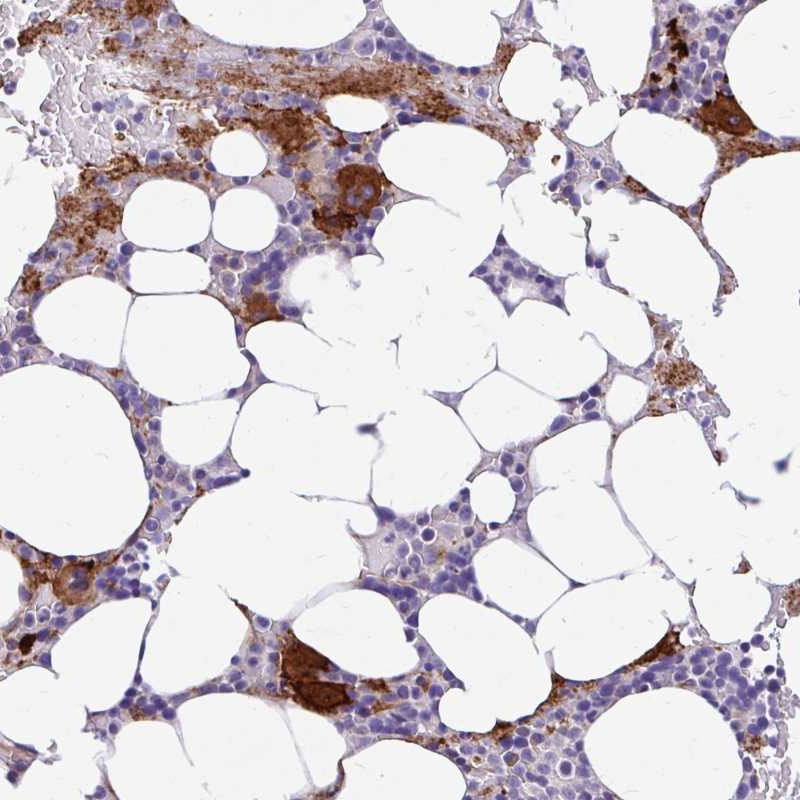

Immunohistochemical staining of human bone marrow shows strong cytoplasmic positivity in megakaryocyte.